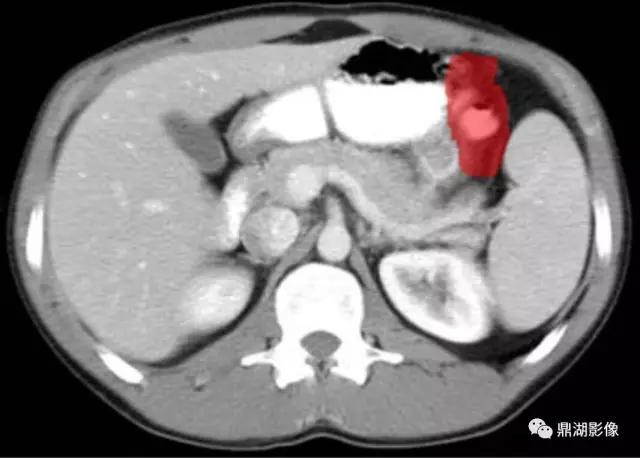

脾区(Splenic Flexure)

肝曲(Hepatic Flexure)